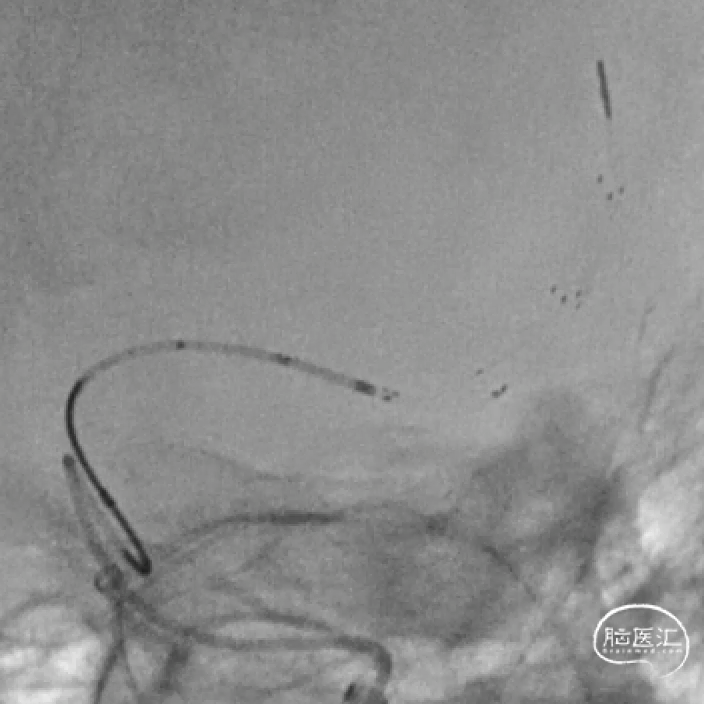

EmboTrap3 5*37mm支架到位后,回撤微导管进行释放,造影提示闭塞段重度狭窄。

支架锚定后,将中间导管推进到支架近端,抽拉结合取栓,可见支架捕获血栓。再次造影血管再通,M1段仍残余重度狭窄。

观察1小时后,血流速度满意,mTICI 3级。结束手术。